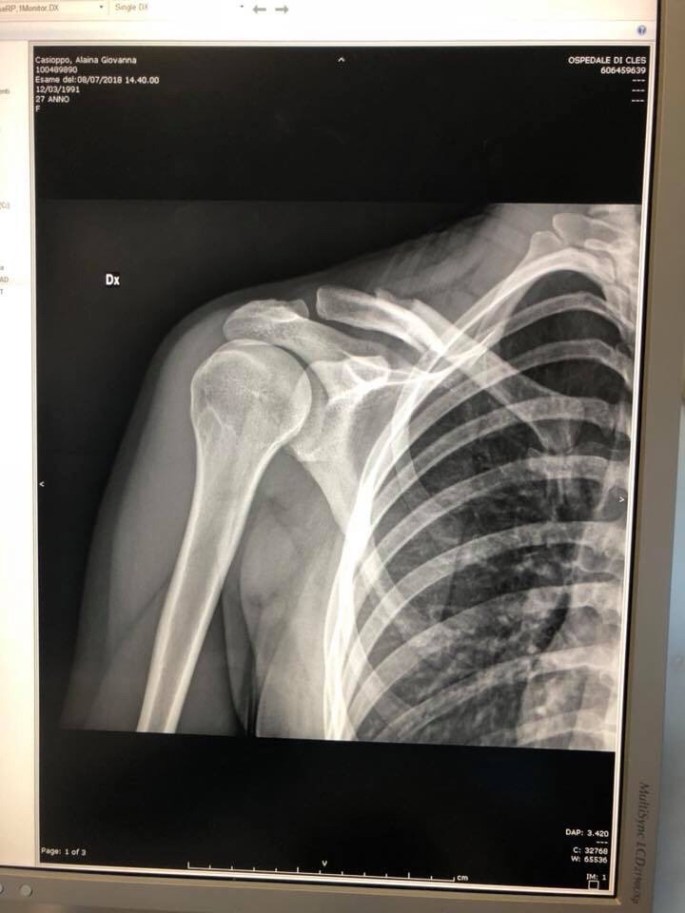

Back in June of this year, 2018, I went to my first UCI World Cup mountain bike race in Nove Mesto, Czech Republic. Prior to leaving admits the mad rush to pack all my things I went out and bought a good old fashioned journal. What better way to write down all my thoughts, experiences and general word vomit on all the long flights and pre-race resting, right!? This was going to be the perfect platform to get all my ideas out in the moment, a great way to remember all the little details and then pull the good parts out later to share. Well it worked out great until race #2 in Val di Sole, Italy. An unfortunate crash shattered my collarbone and I was unable to write. Now how are you supposed to journal and get all my ideas out there if I’m limited to writing with my left hand at the pace of a snail and in what only slightly resembles the English alphabet. Therefor I started this blog. So let’s see how it goes and I look forward to sharing my word vomit with you all! Be prepared, 90% of what I write will likely be about bikes…I am slightly obsessed!